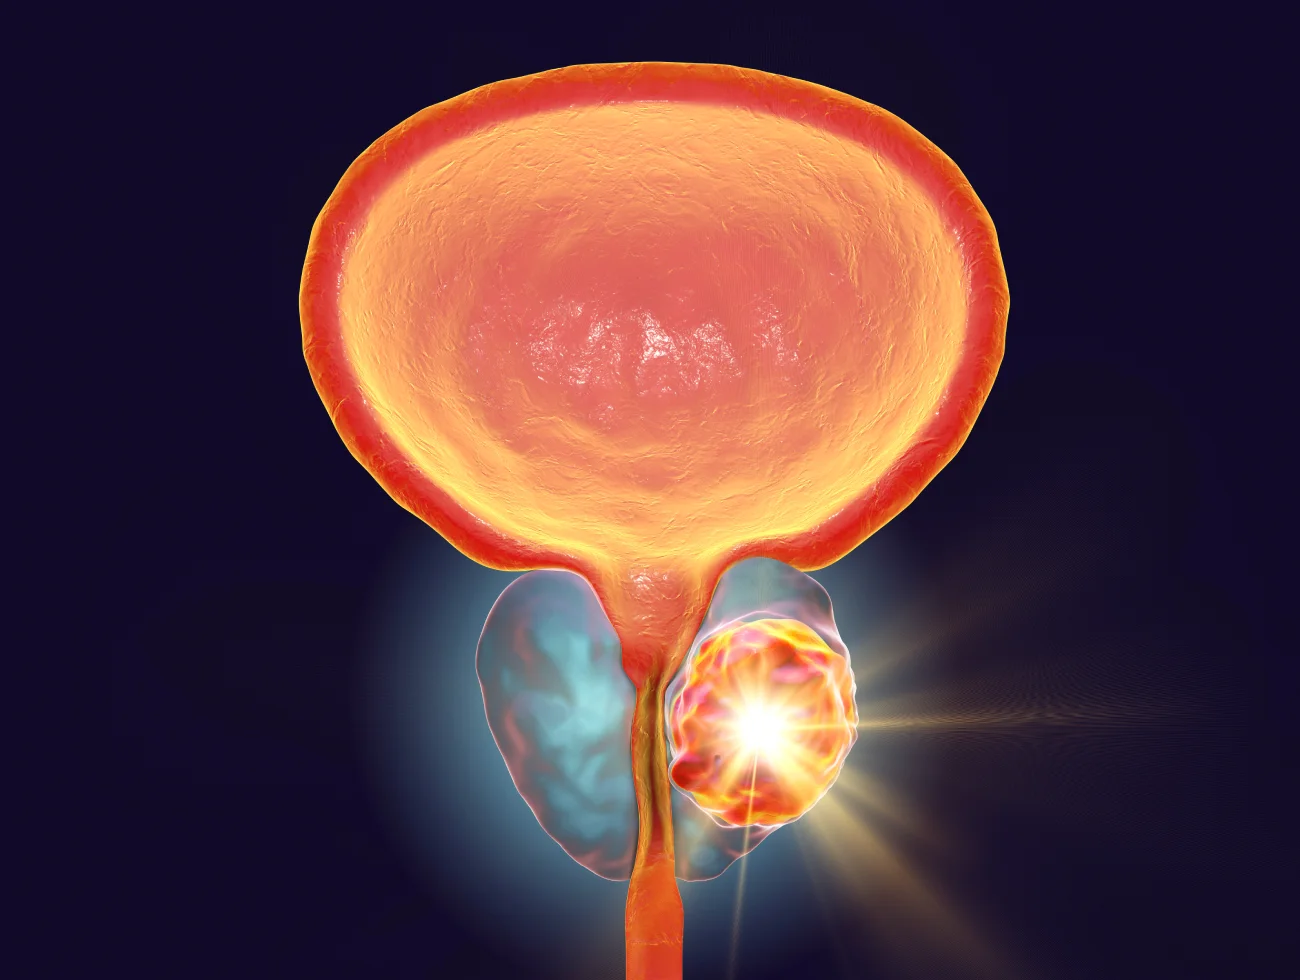

Prostate cancer has become the second most common type of cancer affecting men (skin cancer is the most prominent for men), with approximately 240,000 patients diagnosed each year, The market is witnessing growth due to factors such as the adoption of novel screening and diagnostic technologies, and government support for new therapies to cure prostate cancer. The adoption of novel screening and diagnostic technologies is projected to promote the adoption of new therapeutics. Recent breakthroughs in therapies use bioinformatics and computational biology technologies to obtain optimal treatment.

For additional information on Prostate Cancer, please review the video by Medical Centric.